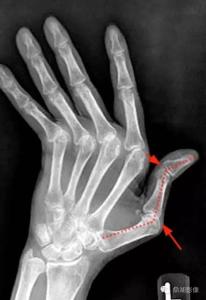

类风关可表现为关节肿胀、压痛、晨僵(早上刚起床关节僵硬,需要过一会儿才能活动)、畸形,严重时丧失劳动能力。此外,该病还会引起疲劳、血红蛋白降低等全身症状。统计显示,如果不经过治疗,类风关的两年致残率达到50%,3年可达70%。